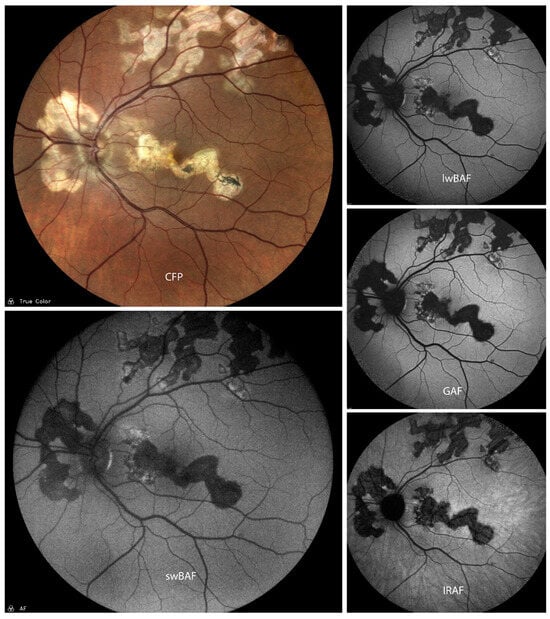

3.1.5. Serpiginous Choroiditis (SC)